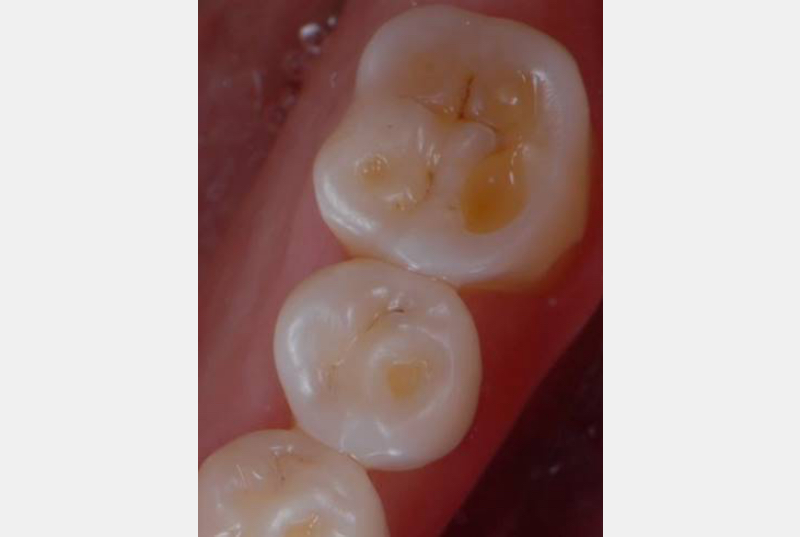

Self-induced vomiting increases the risk of dental erosion by a factor of 5.5 compared to healthy controls. These intrinsic erosion lesions are most commonly found on the palatal surfaces of the maxillary teeth, followed by the occlusal and then the buccal surfaces (Figs. 1–5).

One additional procedure we usually use to increase patients’ awareness is to show a still image from the Patient Education video alongside a photograph of the patient’s clinical condition. This truly helps them visualize and further understand the need for therapy and the harmful potential consequences of inaction.